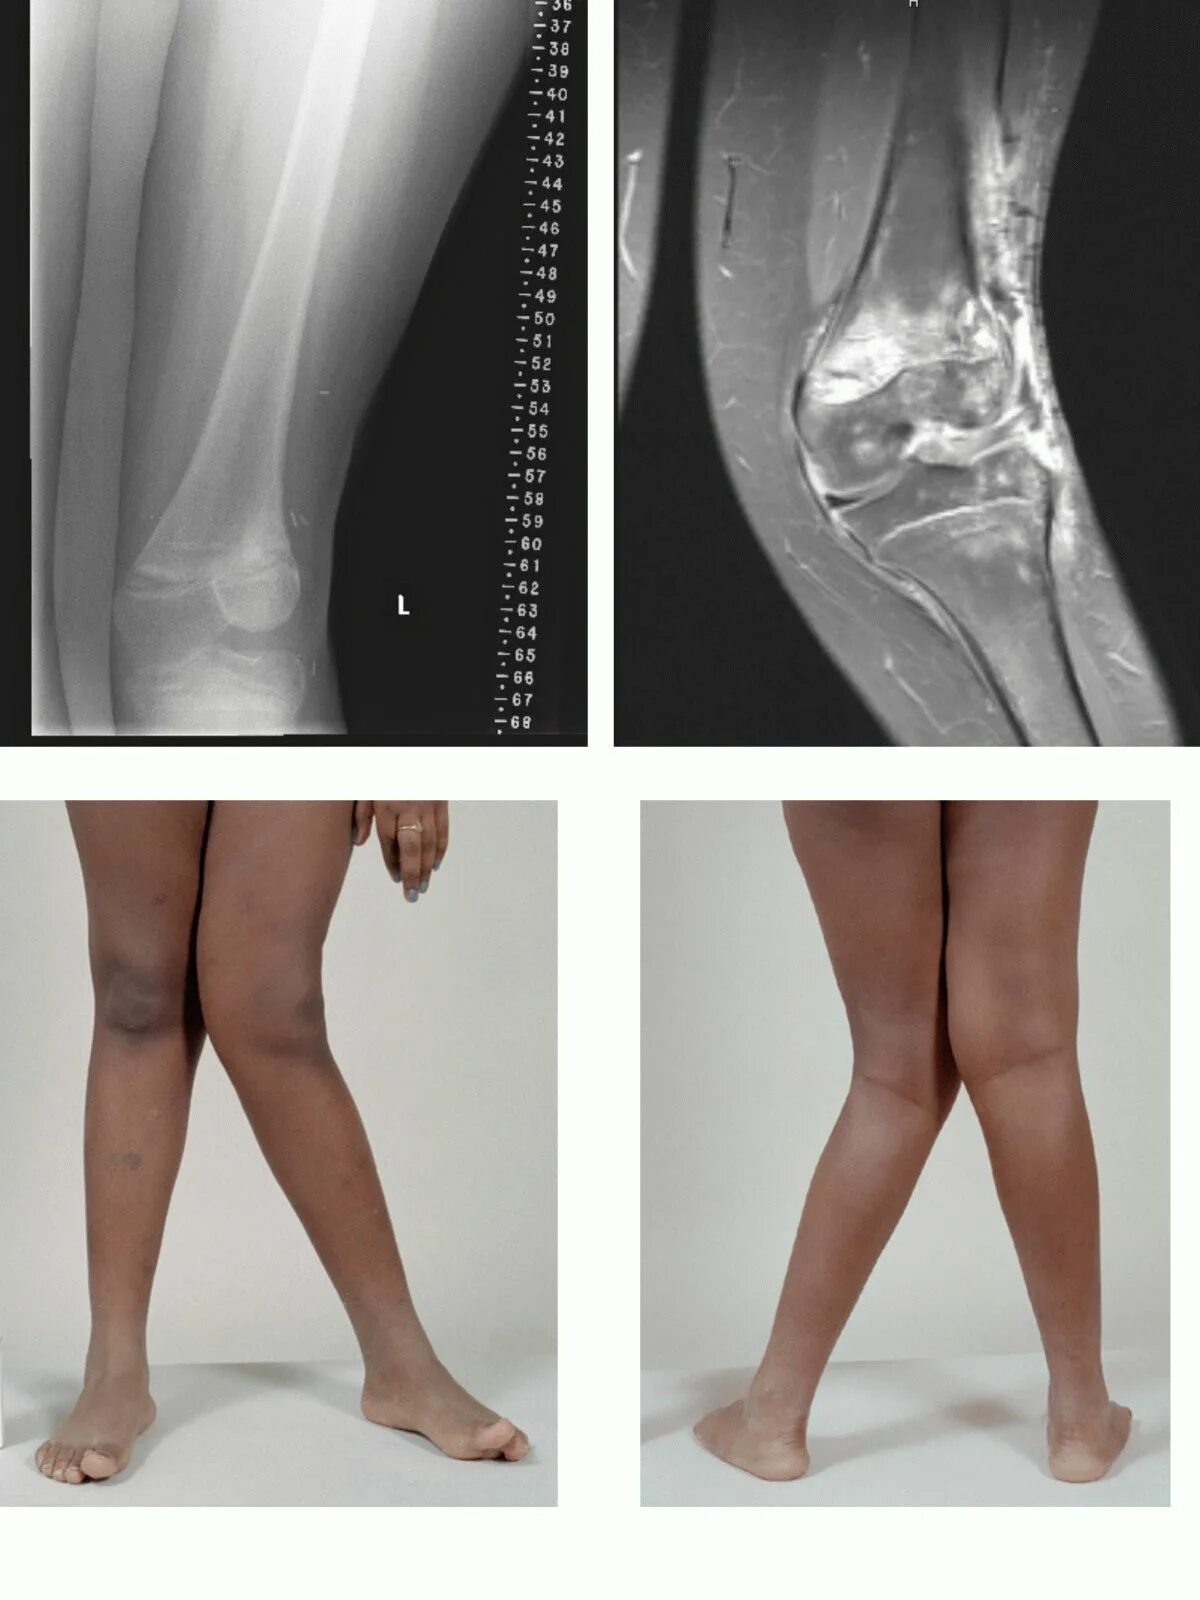

Варусная деформация голени рентген. вальгусная деформация и варусная деформация. варусная деформация коленных суставов.

Варусная деформация коленных суставов. варусная деформация большеберцовой кости. вальгусная и варусная деформация стопы. вальгус коленных суставов.

Варусная дисплазия коленных суставов. дисплазия эрлахера блаунта. варусная деформация голени. варусная деформация нижних конечностей.